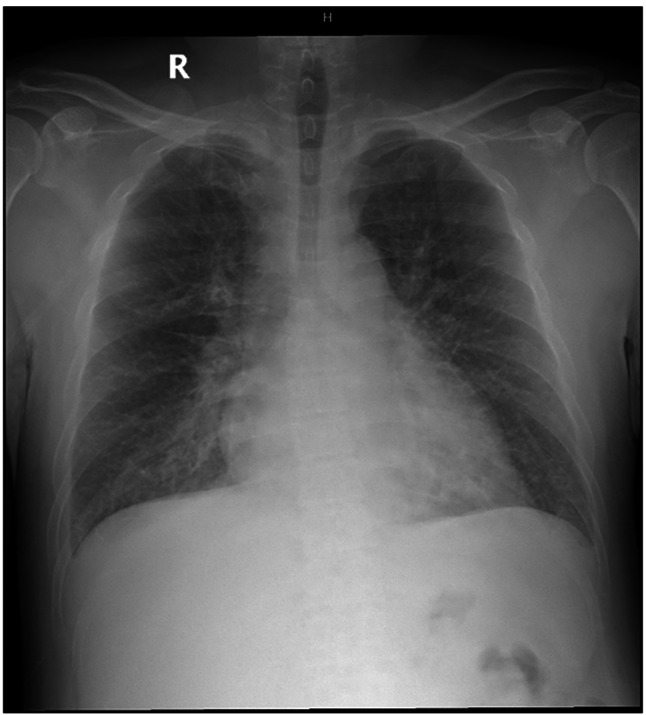

Case presentation: A 42-year-old Vietnamese man developed abdominal distension, facial edema, and dyspnea after initiation of Helicobacter pylori eradication therapy. Imaging revealed pleural, pericardial, and peritoneal effusions, periportal edema, and interstitial pulmonary edema. Laboratory results showed hyponatremia, hypoalbuminemia, and mild anemia. Autoimmune screening revealed ANA positivity (1:80, speckled) and lupus anticoagulant, though extractable nuclear antigens were negative. The patient improved rapidly with corticosteroids and antihistamines.